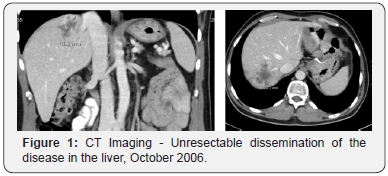

The 49-year-old female was diagnosed with metastatic rectal adenocarcinoma with liver metastases in April 1995 and underwent the resection of the primary tumor and liver metastases, stage T3N2M1, after preoperative chemoradiotherapy with 5-Fluorouracil (5-FU) and Cisplatin. Year 2000 at progression, the second resection of the solitary liver metastasis (mets) was performed. In May 2004 the mets in scl left near art. Carotis communis was diagnosed and she received radical RT (45Gy) as the disease was inoperabile, afterwards stagnation of the disease was achieved. In October 2006 she presented with Horner Sy, because of the inoperabile disease progression in the left scl and two mets in the VI and VII part of the liver (Figure 1). From November 2006 till February 2007 she received four cycles of Capecitabin and Irinotecan (XELIRI) in combination with bevacizumab. The Horner Sy disappeared. The control CT of the thorax and abdomen has showed partial response of the disease in the left scl and in the liver, so the metastasectomy of the liver mets followed in March 2007. She continued with two additional cycles of XELIRI + bevacizumab till May 2007. At that time the beta blocator and thyroxin substitution was introduced as regular therapy by the cardiologyst because of tachicardia as late side effect of received RT of the left scl. In June 2007 asymptomatic pulmonary microembolisms were diagnosed and she started with therapeutic doses of low weight heparin and systemic therapy was discontinued. After one month the condition has normalized, the hearth function remained normal (EF LV 55%) and as the control CT of the thorax and abdomen showed further regression of the disease in the left scl, she received two additional cycles of XELIRI combined with bevacizumab. Afterwards she continued with maintenance monotherapy with bevacizumab.